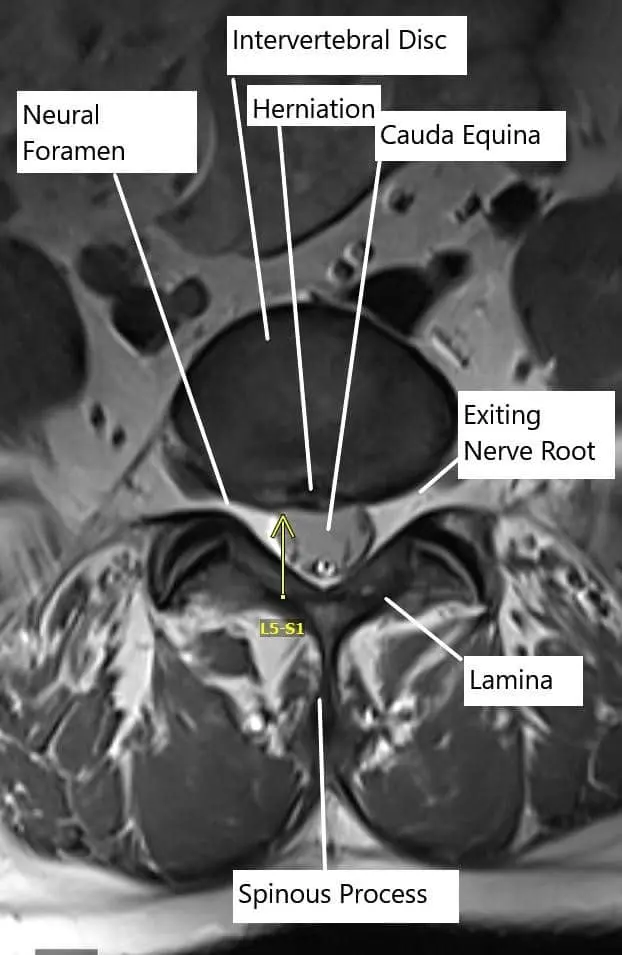

Axial section of the spine showing central disc herniation.